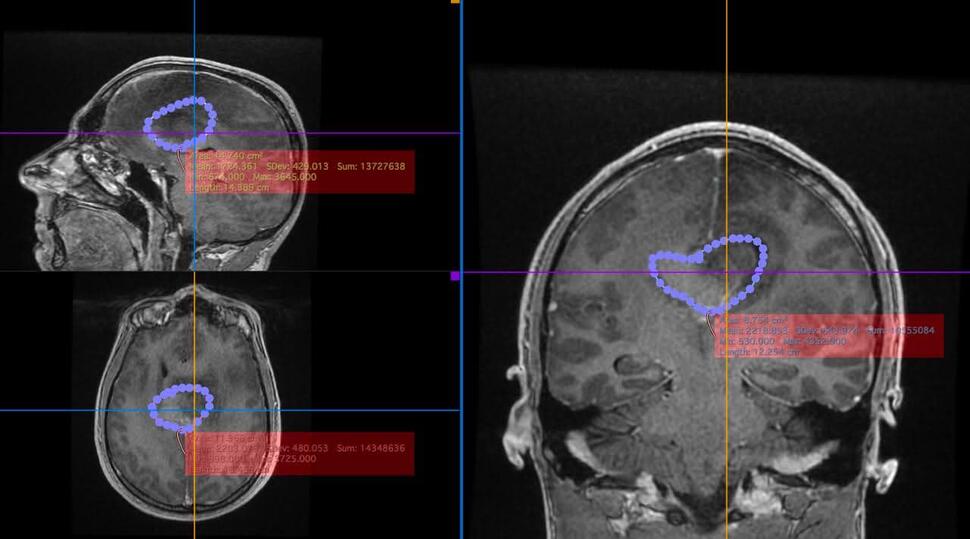

Diagnosticul primit este unul extrem de sever: o tumoră cerebrală agresivă. Din păcate, complexitatea cazului face imposibilă realizarea intervenției necesare în sistemul medical de stat din România. Timpul este un factor critic, iar medicii au fost cât se poate de clari: fără o intervenție chirurgicală de urgență, șansele de supraviețuire sunt minime. Singura opțiune viabilă rămâne o clinică privată specializată, însă costurile operației și ale tratamentului depășesc cu mult posibilitățile sale financiare. Pentru a putea continua demersurile medicale, mai este necesară o sumă de aproximativ 10.000 de euro.